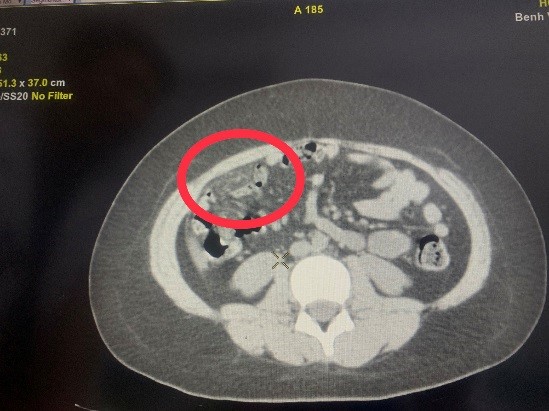

Hình 1,2,3: Hình ảnh theo dõi xoắn mạc nối trên phim chụp CT ổ bụng

khác. Sau đó trẻ được chụp CT ổ bụng để chẩn đoán. Với kết quả ruột thừa bình

thường nhưng có đám viêm nhiễm vùng mạn sườn phải, trẻ đã được các bác sĩ khoa

Ngoại tổng hợp chẩn đoán Xoắn mạc nối lớn và chỉ định mổ cấp cứu bằng phương